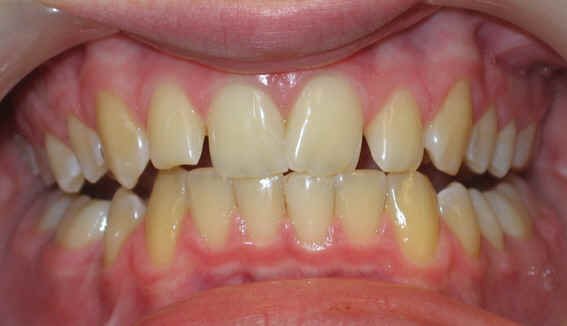

Pre-op 2009/04/18